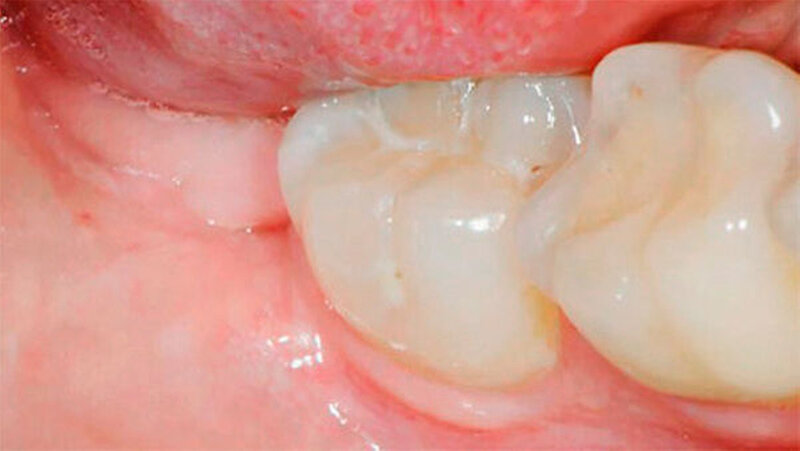

Bei der 27-jährigen, gesunden Patientin, kam es zu rezidivierender Perikoronitis des teilretinierten Zahns 48 (Abb. 1a). Primär wurde eine OPT-Aufnahme zur Operationsplanung erstellt (Abb. 1b). Dabei zeigte sich eine komplette Überlagerung der Zahnwurzel über den C. mandibulae. Zur weiteren Abklärung der Lagebeziehung wurde eine DVT-Aufnahme erstellt (Abb. 1c). Eine linguale Lage des C. mandibulae zur Zahnwurzel konnte festgestellt werden. Eine knöcherne Begrenzung des C. mandibulae zur Zahnwurzel fehlte.

Aufgrund des hohen intraoperativen Läsionsrisikos für den N. alveolaris inferior wurde eine Koronektomie geplant; die Patientin willigte nach eingehender Aufklärung ein. Präoperativ spülte sie mit 0,2 Prozent Chlorhexidin-Mundspülung (Curasept ADS® 220, Curaden AG, Kriens, Schweiz). Eine Leitungsanästhesie des N. alveolaris inferior sowie eine Infiltrationsanästhesie bukkal wurden durchgeführt (Ultracain ds forte, Sanofi-Aventis AG, Vernier, Schweiz).

Die Koronektomie wurde, wie in Abbildungen 1a bis k gezeigt, durchgeführt. Die Schnittführung erfolgte intrasulkulär beim Nachbarzahn mit kurzer disto-bukkaler Entlastung über dem Ramus ascendens. Anschließend wurde ein bukkaler Mukoperiostlappen gebildet. Die Zahnkrone, welche von Knochen bedeckt war, wurde mit dem Handstück und dem Rosenbohrer unter ständiger NaCl-Kühlung bis zur Schmelz-Zement-Grenze freigelegt.